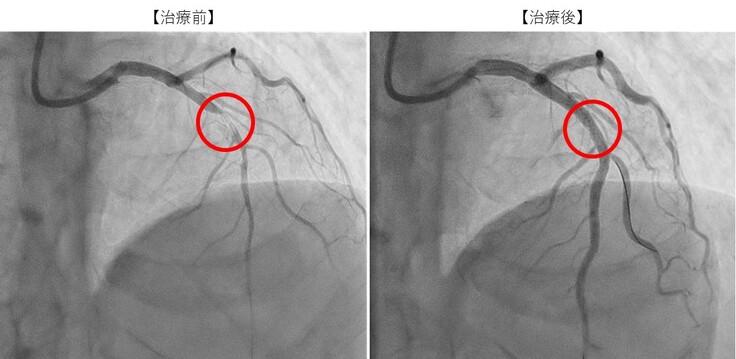

当院での検査の結果、下記の画像の通り、冠動脈が閉塞しておりそのままカテーテル治療を施行しました。